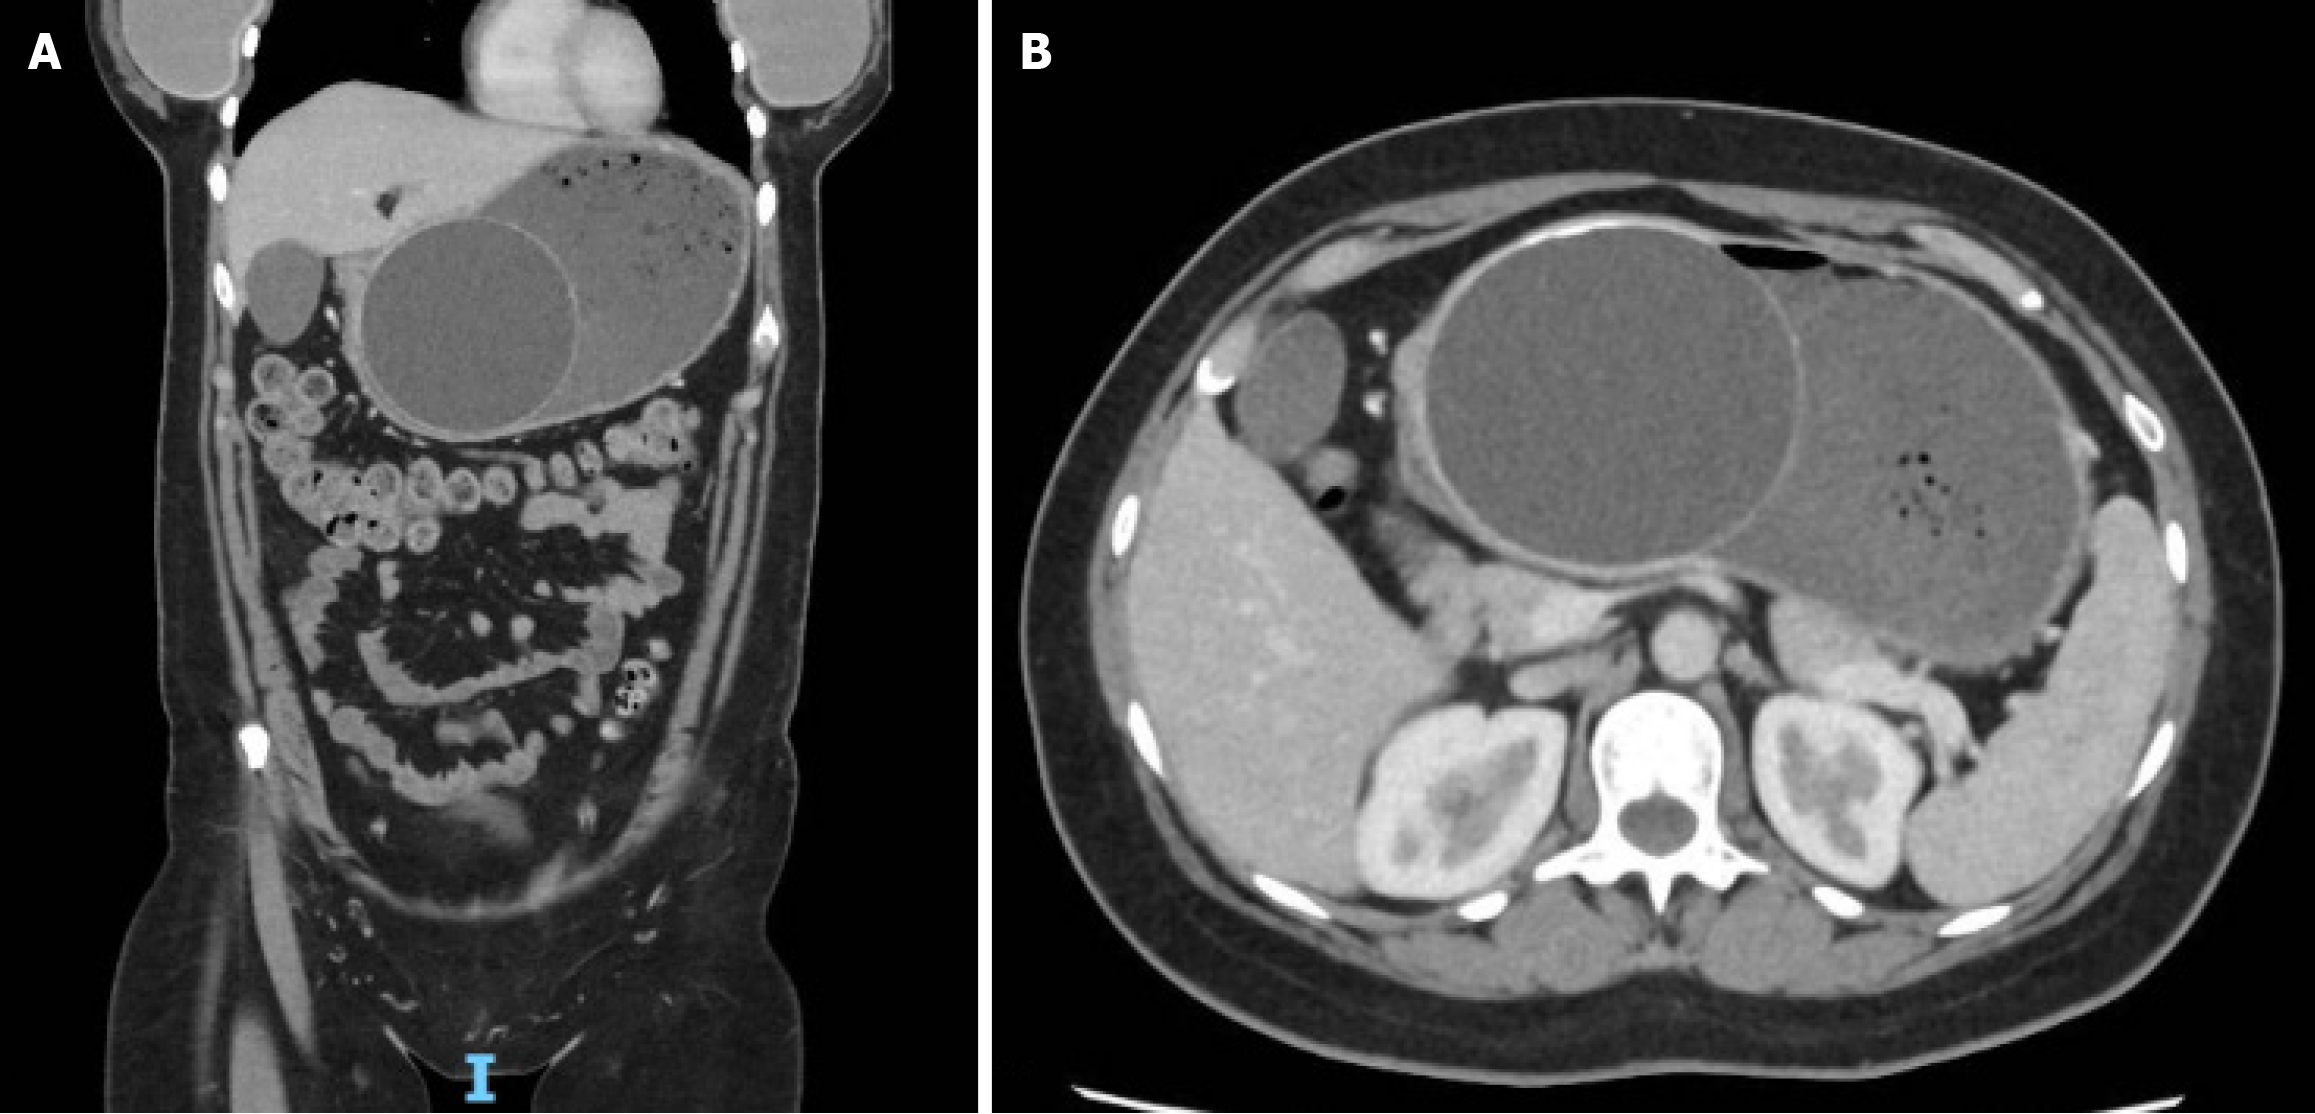

Figure 2 Imaging examinations.

A, B: Coronal and axial computer tomography abdomen demonstrating Silimed intragastric balloon in antrum and prepyloric region of the stomach with associated proximal dilatation and gastric contents.